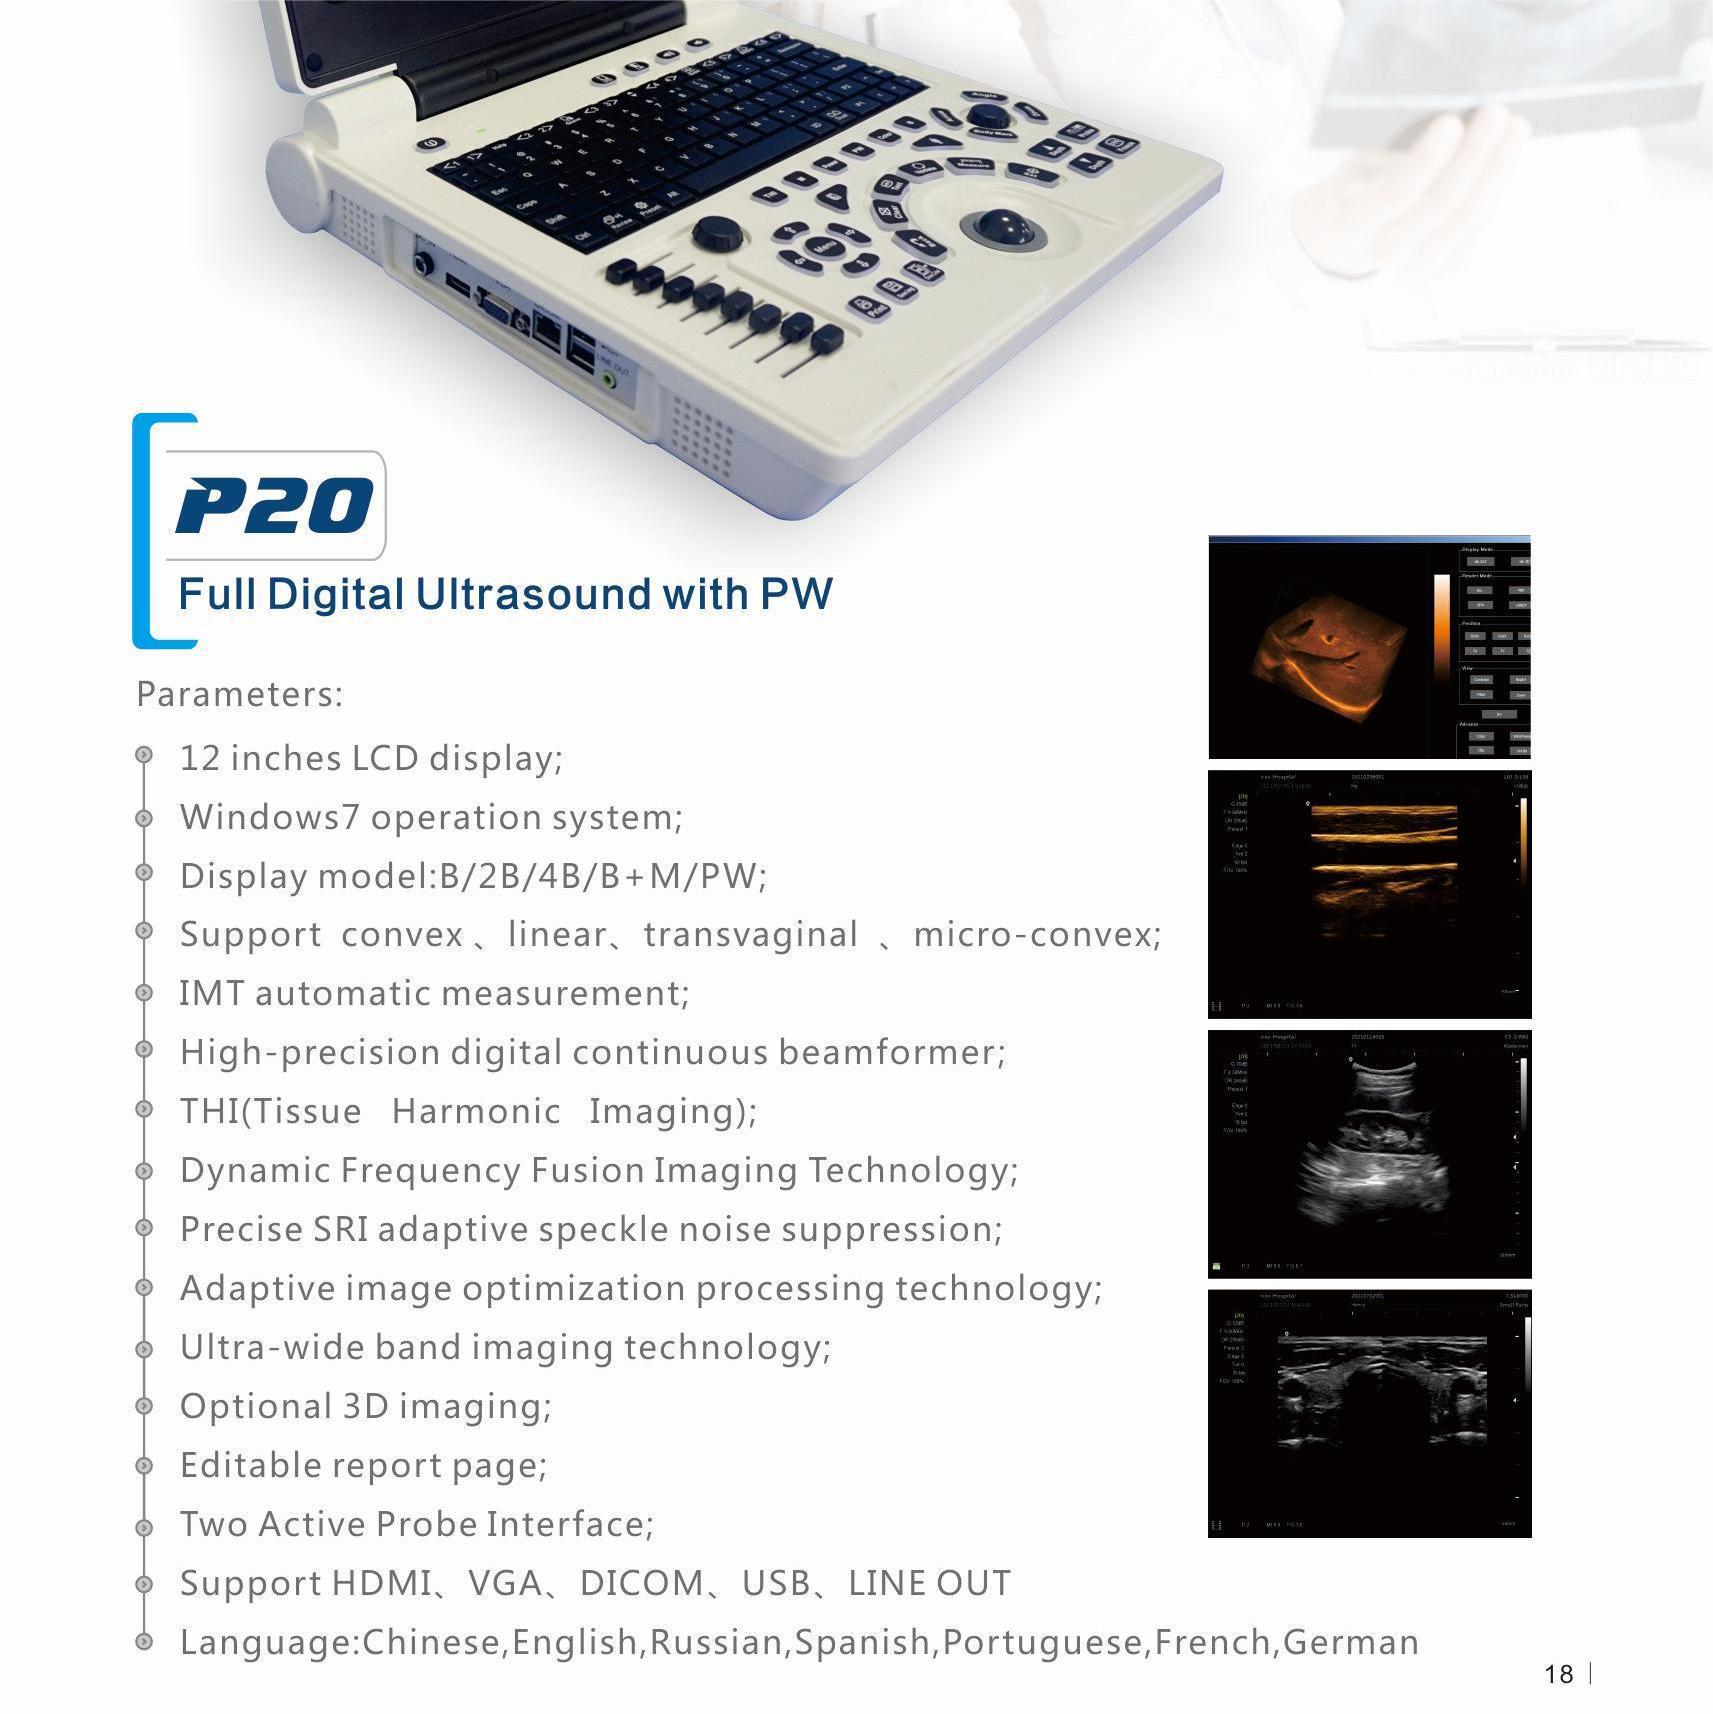

Портативный ультразвуковой аппарат Animal B; Выпуклый массивный зонд; Линейный зонд; Слегка выпуклый зонд; ректальный зонд